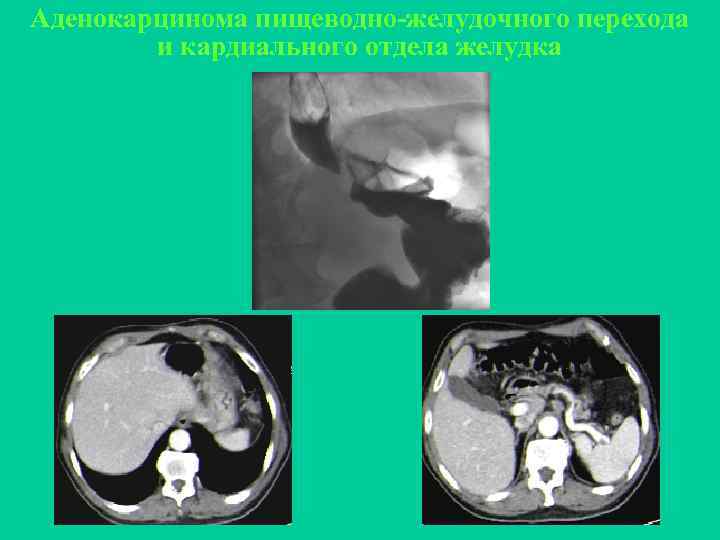

Аденокарцинома пищеводно-желудочного перехода и кардиального отдела желудка